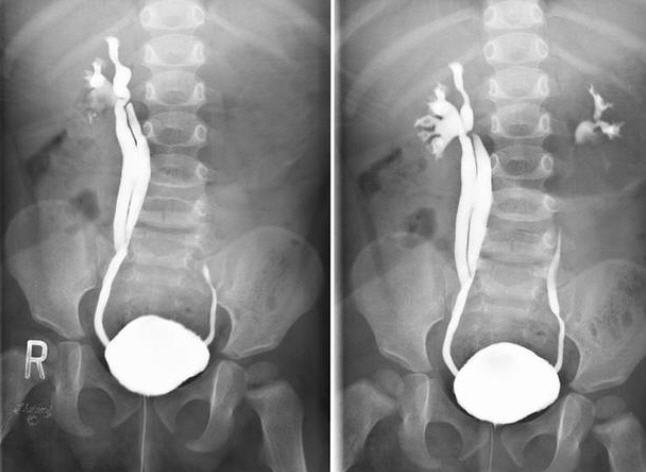

Есть признанный и довольно успешно себя зарекомендовавший метод исследования организма на предмет присутствия пузырно-мочеточникового рефлюкса – это микционная цистография.

Ее суть заключается в том, что через уретральный катетер через мочеточник в полость мочевого пузыря вводится контрастирующее вещество и проводится рентгенологическое исследование. Тогда становится понятно жидкостное движение в мочевом пузыре, и так выясняется наличие данной патологии.

При рефлюксе, как правило, не дают эффекта обычные ультразвуковые исследования и магнитно-резонансная томография. А вот микционная цистография по стоимости довольна доступна и проста в исполнении, так что выполнить ее можно почти в любом профильном медицинском учреждении.